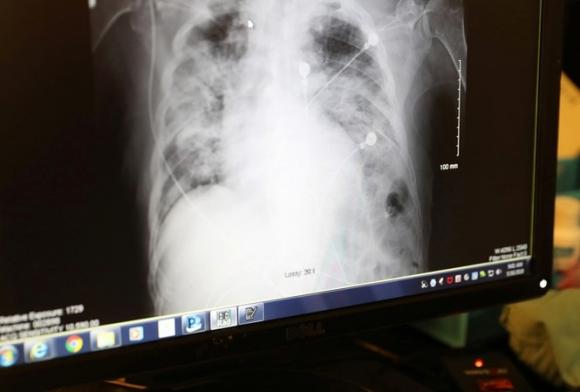

Ảnh minh họa